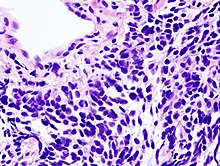

Lung cancers are classified according to histological type.[12] This classification is important for determining both the management and predicting outcomes of the disease. Lung cancers are carcinomas – malignancies that arise from epithelial cells. Lung carcinomas are categorized by the size and appearance of the malignant cells seen by a histopathologist under a microscope. For therapeutic purposes, two broad classes are distinguished: non-small-cell lung carcinoma and small-cell lung carcinoma.[69]

Non-small-cell lung carcinoma[edit | edit source]

Micrograph of squamous-cell carcinoma, a type of non-small-cell carcinoma, FNA specimen, Pap stain

The three main subtypes of NSCLC are adenocarcinoma, squamous-cell carcinoma, and large-cell carcinoma.[2] Rare subtypes include pulmonary enteric adenocarcinoma.[70]

Nearly 40% of lung cancers are adenocarcinoma, which usually comes from peripheral lung tissue.[12] Although most cases of adenocarcinoma are associated with smoking, adenocarcinoma is also the most-common form of lung cancer among people who have smoked fewer than 100 cigarettes in their lifetimes ("never-smokers")[2][71] and ex-smokers with a modest smoking history.[2] A subtype of adenocarcinoma, the bronchioloalveolar carcinoma, is more common in female never-smokers, and may have a better long-term survival.[72]

Squamous-cell carcinoma causes about 30% of lung cancers. They typically occur close to large airways. A hollow cavity and associated cell death are commonly found at the center of the tumor.[12]

About 10 to 15% of lung cancers are large-cell carcinoma.[73] These are so named because the cancer cells are large, with excess cytoplasm, large nuclei, and conspicuous nucleoli.[12]